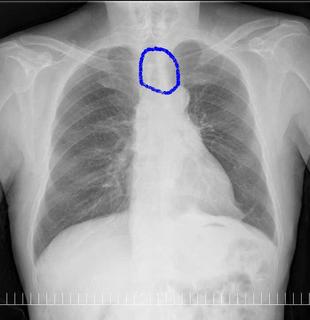

こちらを見て下さい。

わかりにくいかもしれませんが、このあたり。

気管が追いにくい、無くなっているようにも見えます。